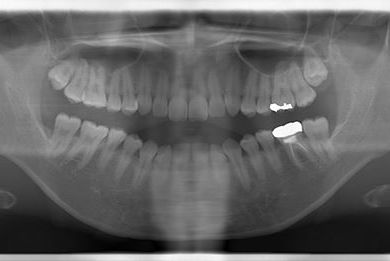

性別/年齢 女性 / 32歳

主訴 銀歯を白い歯にしたい。

治療方針 セラミック治療にて、審美的回復を行う。

治療内容 ハイブリッドセラミッククラウン1本、ハイブリッドセラミックインレー1本

治療部位

6

総治療費 89,250円

治療期間 4ヶ月